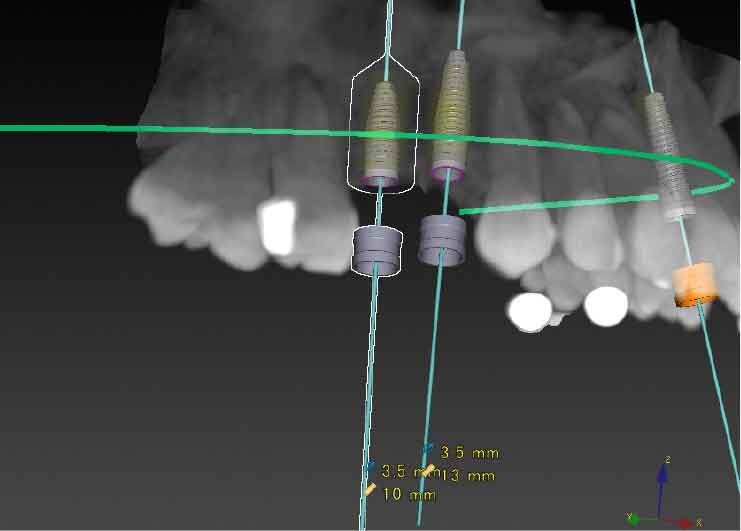

CTスキャンを撮影後、DTX Studioによる手術シミュレーションを行い、X-ガイドによるナビゲーション手術を行いました。

CTスキャンを撮影後、DTX Studioによる手術シミュレーションを行い、X-ガイドによるナビゲーション手術を行いました。

CTスキャンを撮影後、下歯槽神経の位置を明示した3D模型を作製。

DTX Studioで、下歯槽神経の位置とインプラントの埋入方向、深度を詳細に検討し、神経にダメージを与えないインプラントの位置をシミュレーション、X-ガイドによるナビゲーション手術を行いました。

DTX Studioで、下歯槽神経の位置とインプラントの埋入方向、深度を詳細に検討し、神経にダメージを与えないインプラントの位置をシミュレーション、X-ガイドによるナビゲーション手術を行いました。